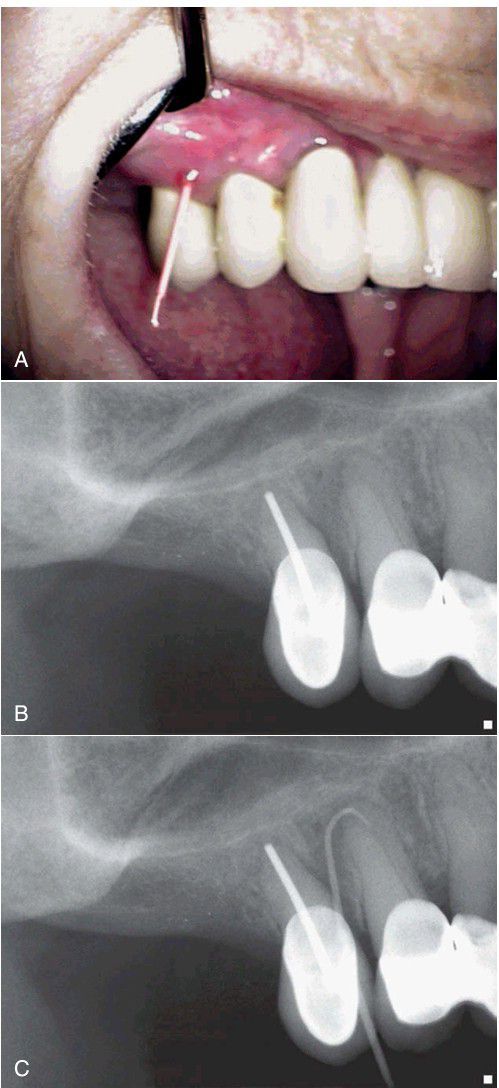

, To locate the source of an infection, the sinus tract can be traced by threading the stoma with a gutta-percha point. B, The radiograph of the area shows an old root canal in tooth #4, and a questionable radiolucent area associated with tooth #5, with no indication of the etiology of the sinus tract. C, After tracing the sinus tract, the gutta-percha is seen to be directed to the source of pathosis, the apex of tooth #5.